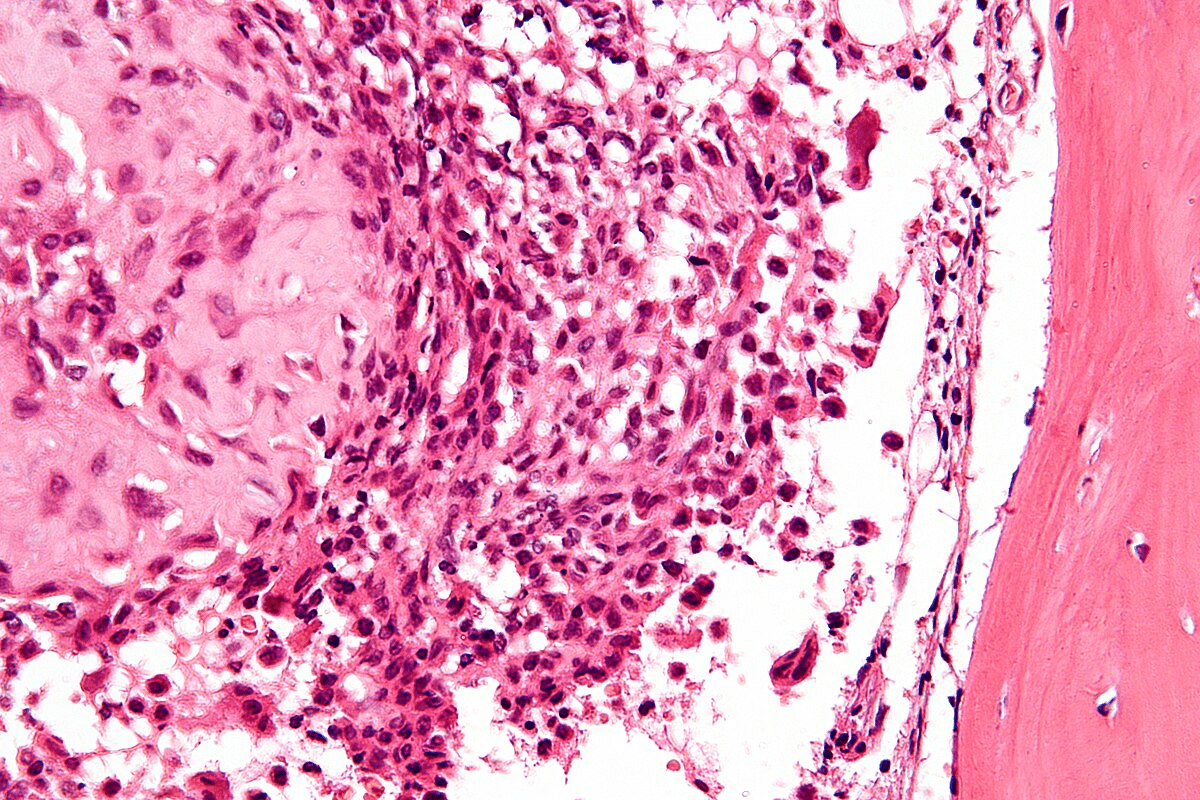

A biopsy is key to confirming bone cancer. We take tissue samples through different methods for detailed checks.

Needle biopsy and surgical biopsy are the main ways. The choice depends on the tumor’s location and size.